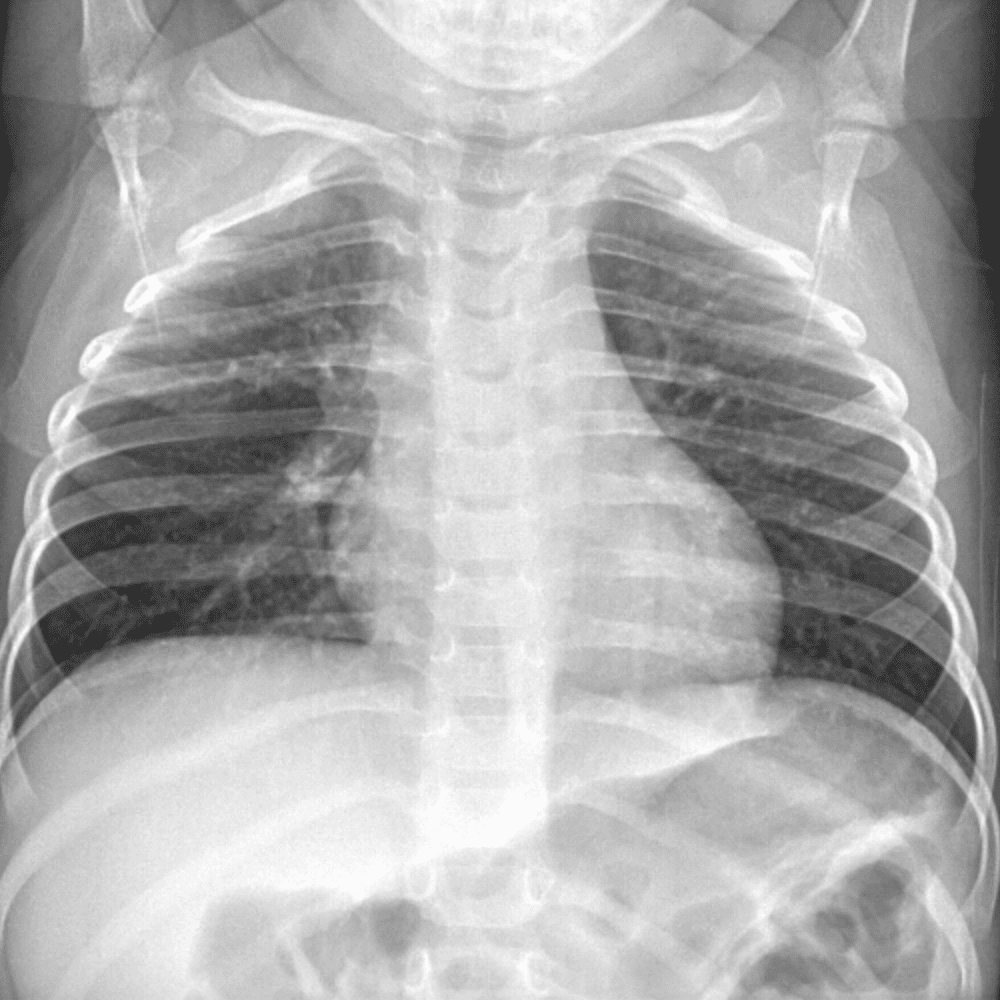

Peds Chest

Practice

Simulates call by including subtle or difficult cases and some normals.

50 cases